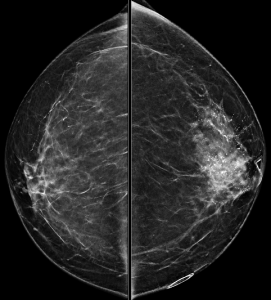

A bilateral diagnostic mammogram is performed for a 56-year-old woman with a left breast palpable abnormality and pain:

Other than these whole breast views, what additional views would you like to see in order to make your assessment of the dominant abnormality?

Explanation: There are highly suspicious calcifications in the left breast. In order to best assess the calcifications, spot magnification views are needed, which will allow for a better description of the calcifications’ morphology and distribution.